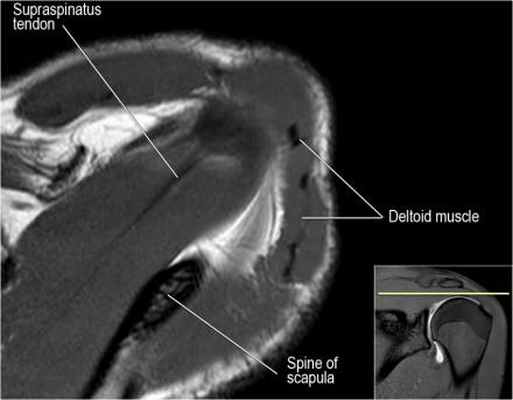

Нормальная анатомия плечевого сустава в аксиальных изображениях и контрольный список.

- поищите os acromiale, акромиальную кость (добавочная кость, расположенная у акромиона)

- обратите внимание что ход сухожилия надостной мышцы параллелен оси мышцы (это не всегда так)

- обратите внимание что ход сухожилия длинной головки двуглавой мышцы в области прикрепления направлен на 12 часов. Область прикрепления может быть различной ширины.

- обратите внимание на верхние отделы суставной губы и прикрепление верхней плече-лопаточной связки. На данном уровне ищется SLAP-повреждение (Superior Labrum Anterior to Posterior) и варианты строения в виде отверстия под сутавной губой (sublabral foramen - подгубное отверстие). На этом же уровне по задне-боковой поверхности головки плечевой кости визуализируются повреждение Хилл-Сакса.

- волокна сухожилия подлопаточной мышцы, создавая бицепитальную борозду, удерживают сухожилие длинной головки двуглавой мышцы. Изучите хрящи.

- уровень средней плече-лопаточной связки и передних отделов суставной губы. Поищите комплекс Буффорда. Изучите хрящи.

- вогнутость заднебокового края головки плечевой кости не следует путать с повреждением Хилл-Сакса, поскольку это нормальная форма для данного уровня. Повреждение Хилл-Сакса визуализируется только на уровне клювовидного отростка. В предних отделах мы сейчас на урвоне 3-6 часов. Здесь визуализируются повреждение Банкарта и его варианты.

- обратите внимание на волокна нижней плече-лопаточной связки. На данном уровне так же ищется повреждение Банкарта.